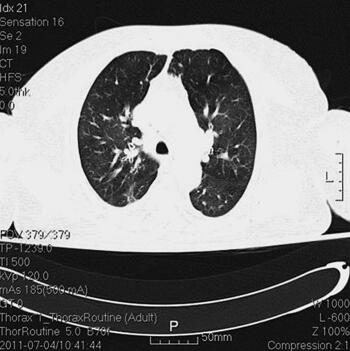

诊治经过:入院后留置右锁骨下深静脉导管,监测CVP。患者血压逐渐平稳,停用多巴胺。继续机械通气,头孢哌酮-舒巴坦钠针剂及阿奇霉素针剂联合抗感染,甲泼尼龙及多索茶碱解痉平喘,改善微循环,化痰等对症支持治疗。并予肠内营养,胰岛素微泵控制血糖。复查胸部CT(7月4日)(图2),感染较前明显吸收;复查(7月4日)CRP 10mg/L,PCT 0.22ng/ml。

图2 胸部CT(7月4日),感染较前明显吸收